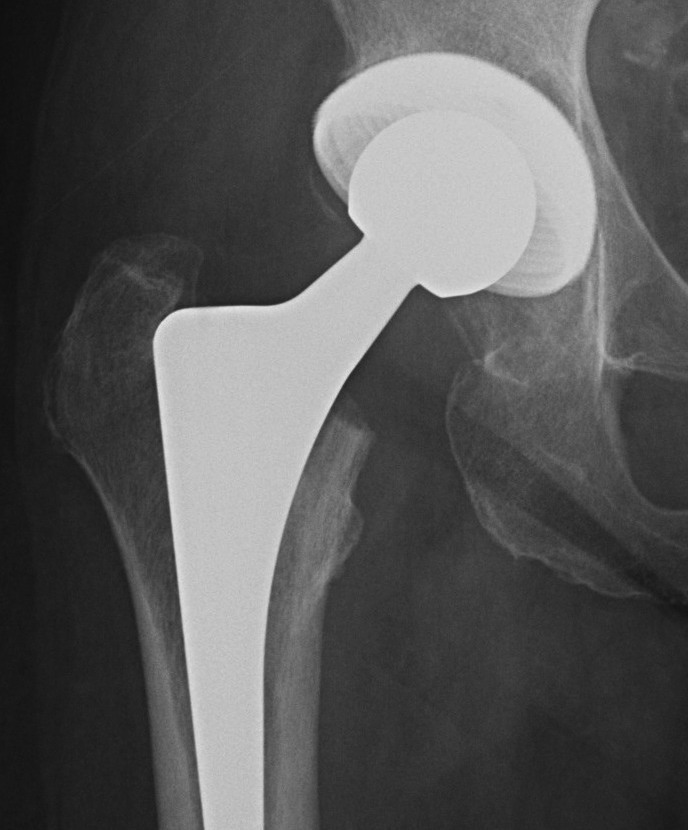

B. Hip resurfacing

See Boneschool page - hip resurfacing

Dislocated resurfacing THA